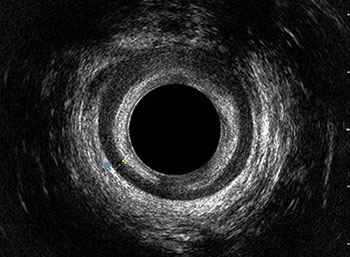

L’ecografia transanale è un esame diagnostico per immagini che consiste nell’introduzione di un trasduttore ad ultrasuoni. Le immagini qualitativamente migliori del canale anale sono ottenute usando un trasduttore rotante, montato in un manipolo rigido, che fornisce un’immagine a 360°. Con le apparecchiature più moderne è anche possibile ottenere immagini tridimensionali.

L’ecografia transanale permette di distinguere la sottomucosa che riveste il canale anale, lo sfintere anale interno, e lo sfintere anale esterno.

Proctal dispone di apparecchiatura per ecografia endoanale 3D con sonda rotante.